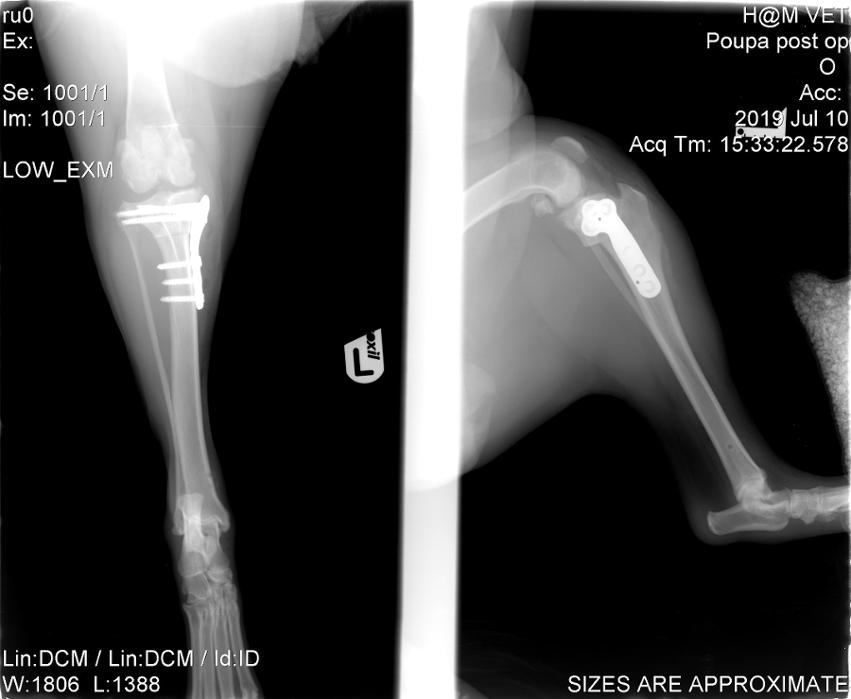

Ορθοπεδική

Ορθοπεδική

Το κτηνιατρείο hm vets αναλαμβάνει ψηφιακή ακτινογραφία, έλεγχο δυσπλασίας ισχίου, ορθοπεδική-νευροχειρουργική, χειρουργική μαλακών μορίων, οφθαλμολογία, εσωτερική παθολογία και εργαστηριακές εξετάσεις (αίματος, βιοχημικές, ανοσολογικές, ορμονολογικες, μοριακές και ιστοπαθολογικές).

Το κτηνιατρείο hm vets αναλαμβάνει ψηφιακή ακτινογραφία, έλεγχο δυσπλασίας ισχίου, ορθοπεδική-νευροχειρουργική, χειρουργική μαλακών μορίων, οφθαλμολογία, εσωτερική παθολογία και εργαστηριακές εξετάσεις (αίματος, βιοχημικές, ανοσολογικές, ορμονολογικες, μοριακές και ιστοπαθολογικές).